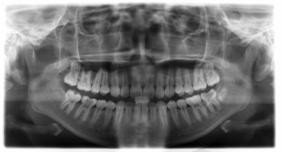

临床诊断:通过数字化全景机的检查,患者的上牙前突属于牙性,双唇闭合时可见明显隆起,X片显示根尖无异常,上下后牙存在间隙,可通过美国MBT直弓丝正畸技术将其矫正复位,并收拢间隙,矫正所需时间一年半左右。